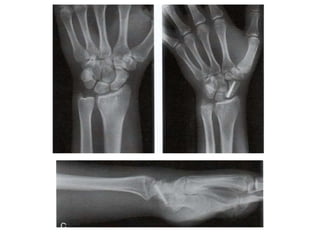

4. Estudios Radiográficos

• 4 proyecciones: AP, L, 2

Oblicuas

• Rx AP: Empuñadura de la

mano con dedos

flexionados

– Plano mas paralelo a la

placa

– Acentúa separación con

semilunar

• Rx AP con

desviación cubital:

Perfil completo de

cintura

• Rx L: alineación y

estabilidad del carpo